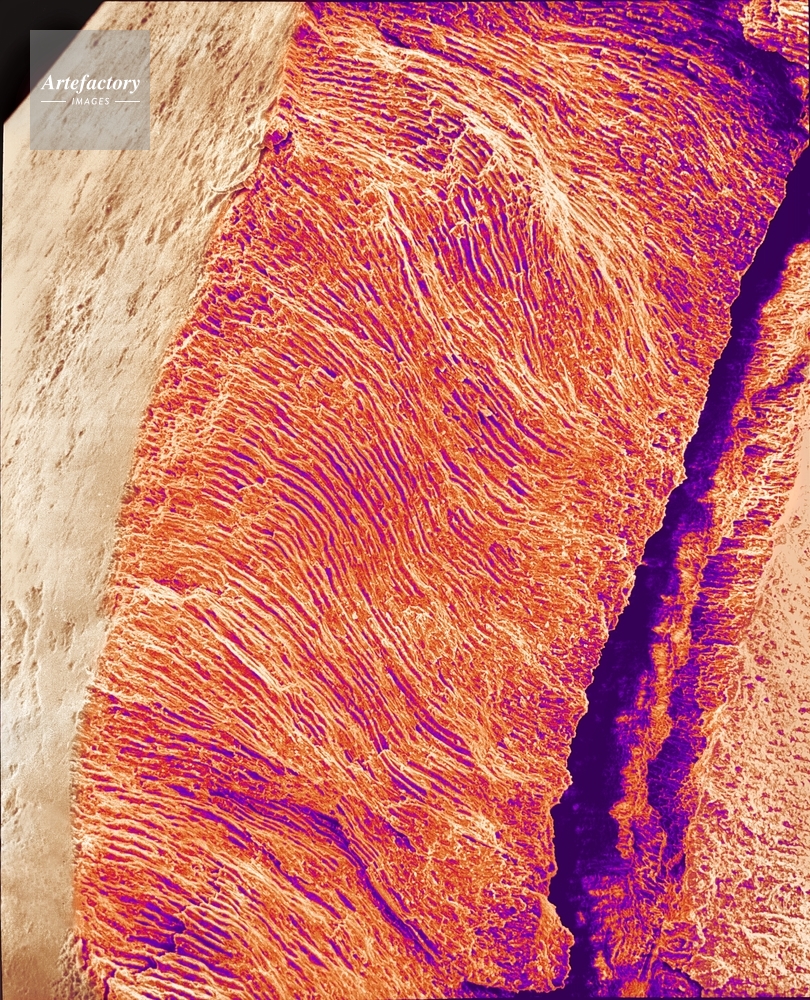

| 作品タイトル | ヒトの歯の断面 | モデルリリース | なし | |

| キャプション | 倍率×140 | 制限事項 | ||